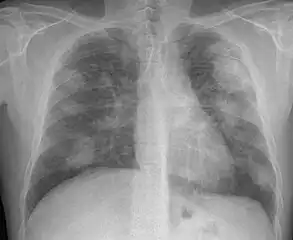

For uncomplicated silicosis, chest x-ray will confirm the presence of small (< 10 mm) nodules in the lungs, especially in the upper lung zones. Using the ILO classification system, these are of profusion 1/0 or greater and shape/size "p", "q", or "r". Lung zone involvement and profusion increases with disease progression. In advanced cases of silicosis, large opacity (> 1 cm) occurs from coalescence of small opacities, particularly in the upper lung zones. With retraction of the lung tissue, there is compensatory emphysema. Enlargement of the hilum is common with chronic and accelerated silicosis. In about 5–10% of cases, the nodes will calcify circumferentially, producing so-called "eggshell" calcification. This finding is not pathognomonic (diagnostic) of silicosis. In some cases, the pulmonary nodules may also become calcified.

Chest X-ray showing uncomplicated silicosis